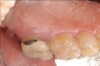

Fig 5. Pre- (Fig 5) and post- (Fig 6) DGV procedure. Note the 7-mm pocket distal to tooth No. 15 before treatment and normal probing depth after treatment. It would have been easier for the restorative dentist to place this crown with increased tooth structure if the tuberosity tissue had been removed previously.

Figure 5

Fig 6. Pre- (Fig 5) and post- (Fig 6) DGV procedure. Note the 7-mm pocket distal to tooth No. 15 before treatment and normal probing depth after treatment. It would have been easier for the restorative dentist to place this crown with increased tooth structure if the tuberosity tissue had been removed previously.

Figure 6

The clinician must determine which of these two harvest techniques should be utilized. Each has its advantages in different situations. For non-wide (buccal-palatal dimension) tuberosities, the DGV technique offers less tissue loss. For wide tuberosities, which are greater than 4 mm in width buccal-lingually and have more CT, the DW technique may be advantageous, as the flap can be approximated and closed with sutures, and this potentially may be more comfortable for the patient. Either technique adequately removes the excess tissue and reduces the pocket. The DGV approach provides a faster tissue harvest and a greater amount of tissue (Figure 5 and Figure 6).